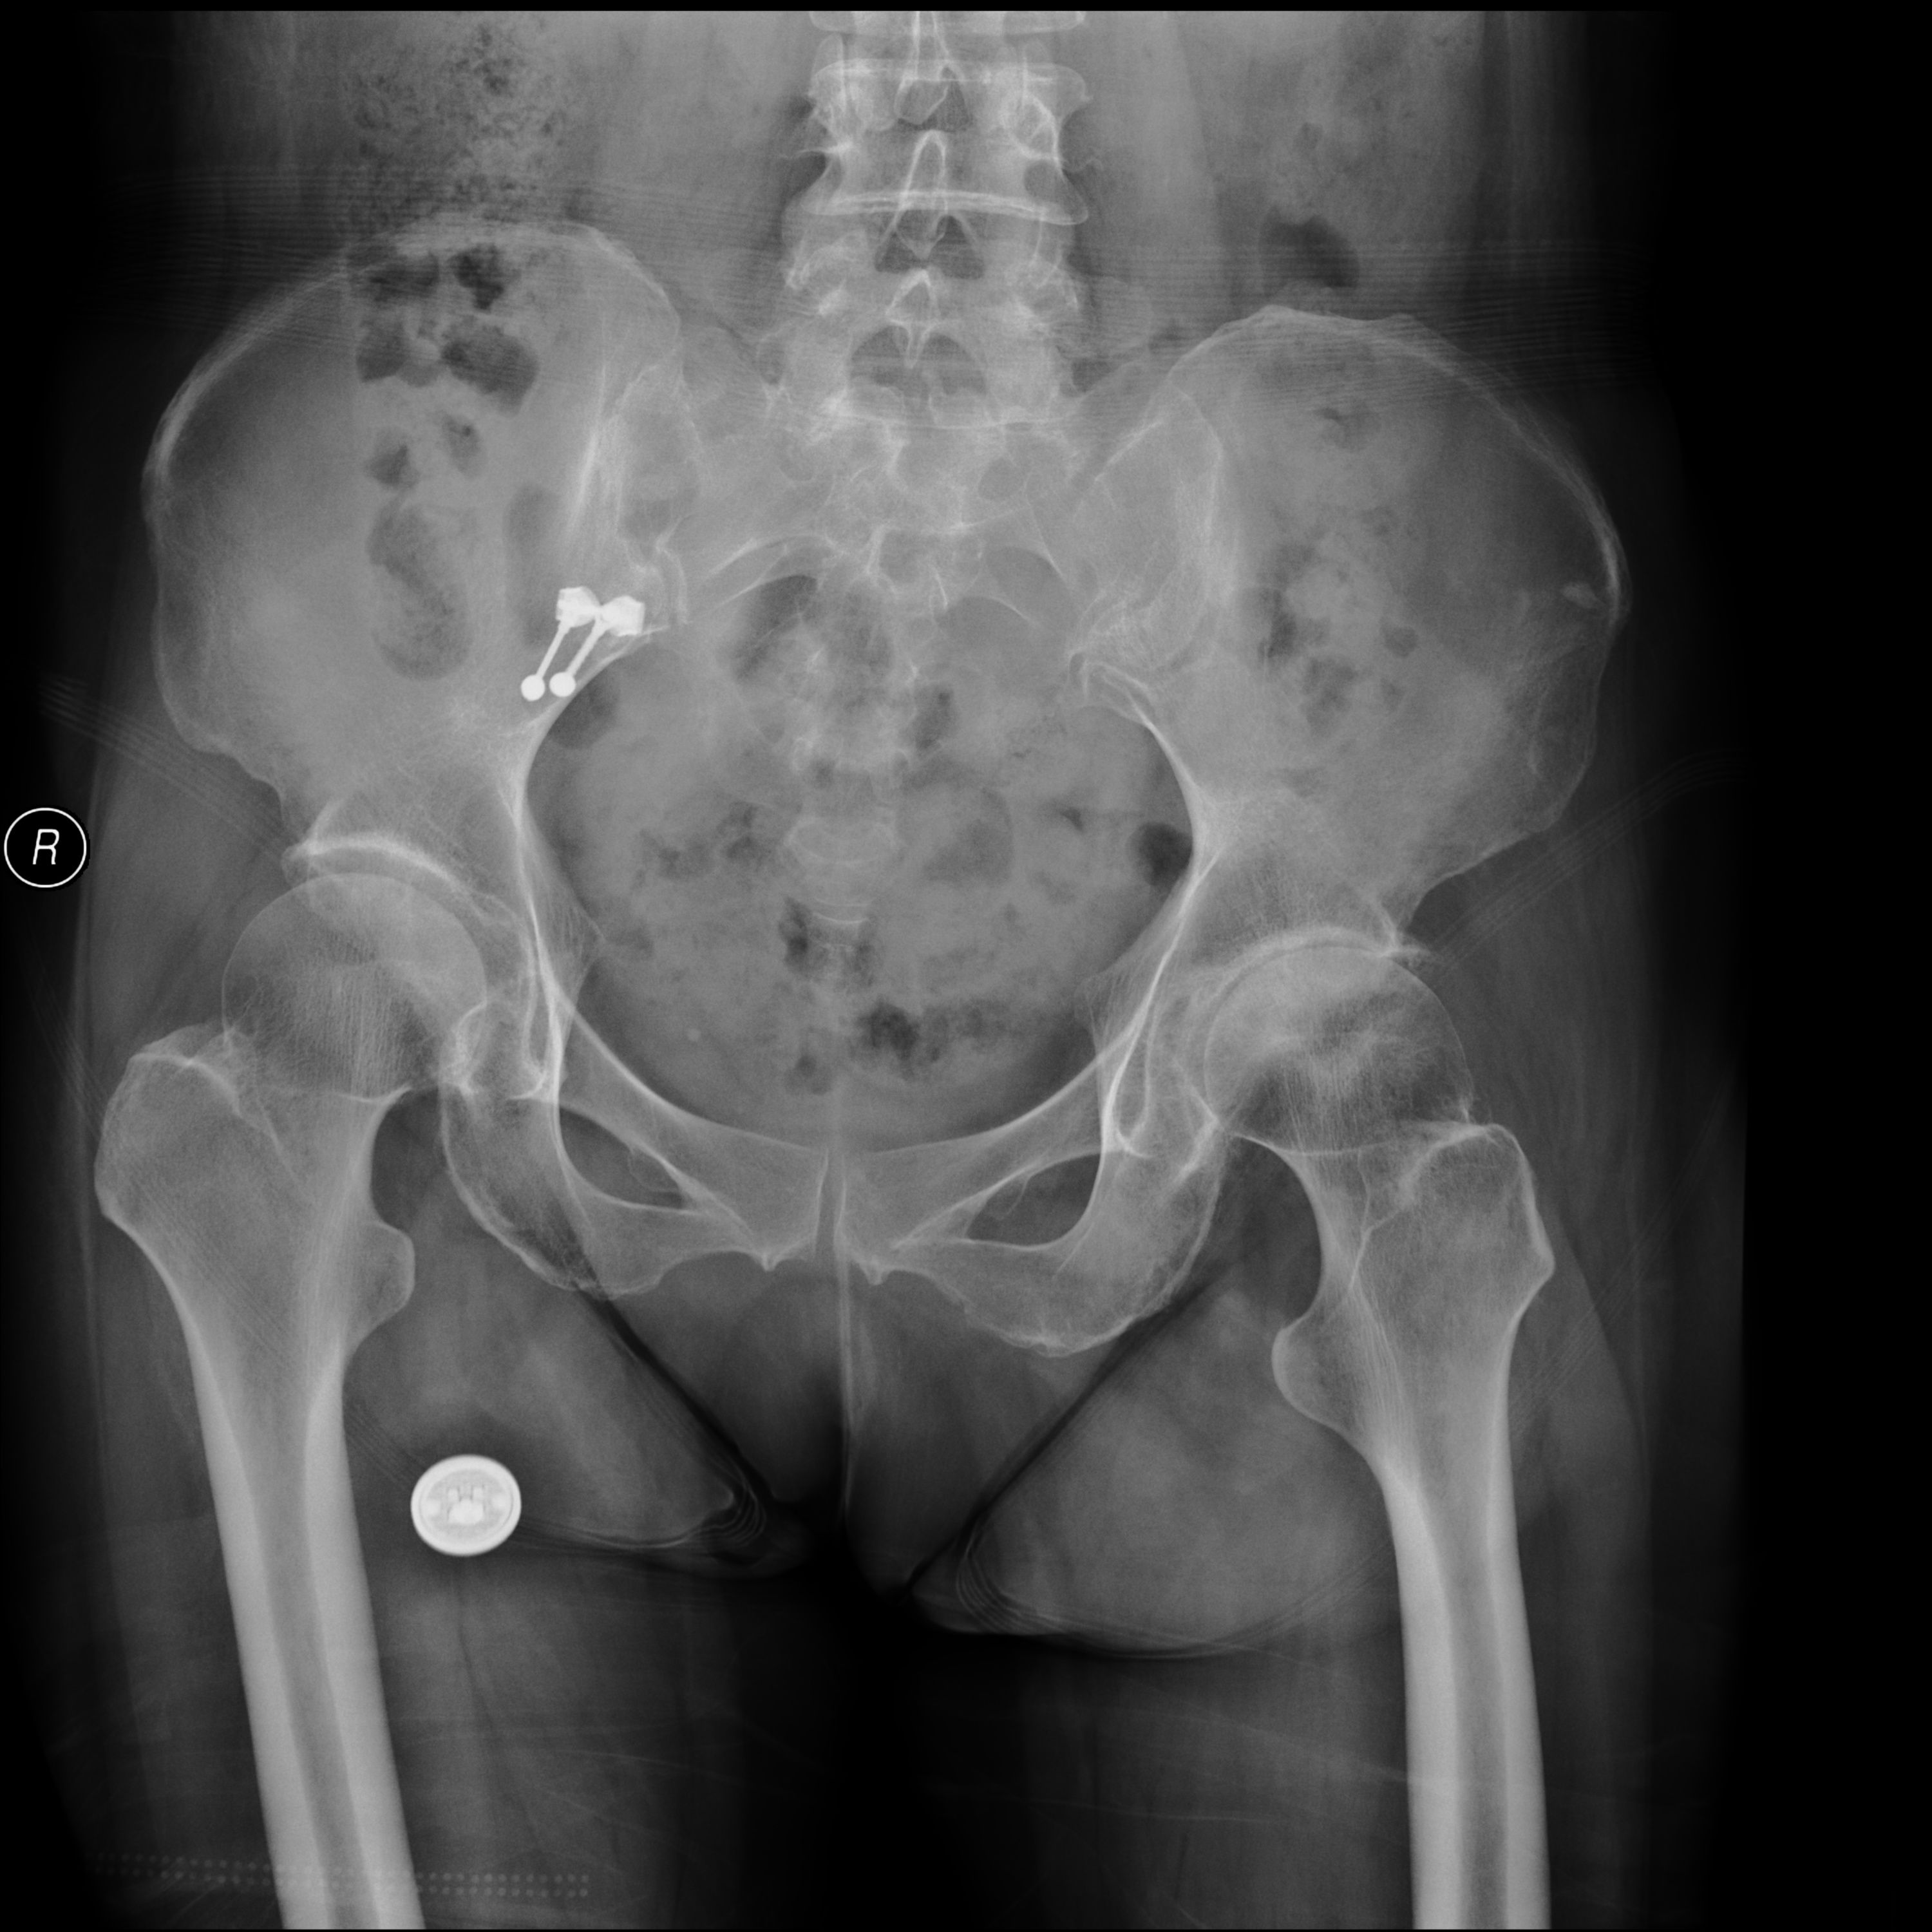

图 髋关节骨性关节炎X片

髋关节骨性关节炎的诊断及治疗,随着人中老年化,肥胖老人越来越多,对于负重的髋关节、膝关节最容易出现退行性变,即所谓的骨性关节炎。膝关节骨质增生已经被人们重视,实际上髋关节骨性关节炎也很多见,重度髋关节骨性关节炎的老年患者只能采取手术治疗。